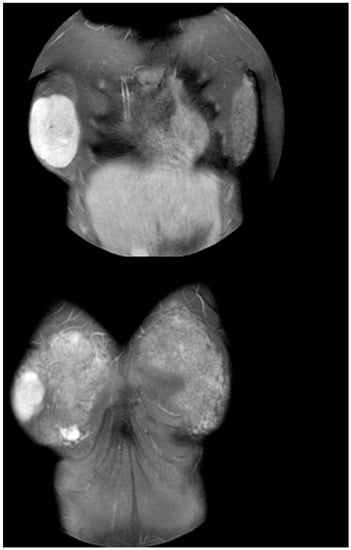

Ultrasound examination of the breast showed a hypoechoic mass in the outer half of the right breast. Its maximum diameter measured 10 cm, with significant internal vascularity. Breast MRI indicated a firm mass, with clear margins and characteristics of a benign mass, most probably a giant fibroadenoma. Its dimensions were calculated as 7.4 cm × 6 cm × 8.1 cm (Figure 2).

Figure 2.

MRI imaging of a 7.4 cm × 6 cm × 8.1 cm mass with clear margins and characteristics compatible with giant fibroadenoma.

The histopathologic evaluation of the surgical specimen confirmed the suspected diagnosis of giant juvenile fibroadenoma. The macroscopic examination revealed a mass with smooth margins. Its dimensions were 10 cm × 8 cm × 2.5 cm (Figure 4). To be noted, the dimensions of the fibroadenoma differed significantly from the ones calculated during the breast MRI and were rather closer to the ultrasonographic estimation. The microscopic examination revealed fibroepithelial composition of the neoplasm. Immunohistochemistry indicated expression of actin and CD34, confirming the stromal origin of one component of the tumor. Simultaneously, epithelial tissue tested positive for estrogen and progesterone receptors, b-catenin and e-cadherin. Ki-67/MIB-1 cellular proliferation markers were detected among 5–10% of fibrous cells. During the follow-up consultation, breast development was normal and symmetrical. In addition, the patient reported satisfaction with the aesthetic result. Interestingly, the patient’s period started one month after the operation. Table 1 presents the 87 cases of giant juvenile fibroadenomas which were included in our review [,,,,,,,,,,,,,,,,,,,,,,,,,,,,,,,,,,,,,,,,,,,,,,,,,,,,,,,,,,,].